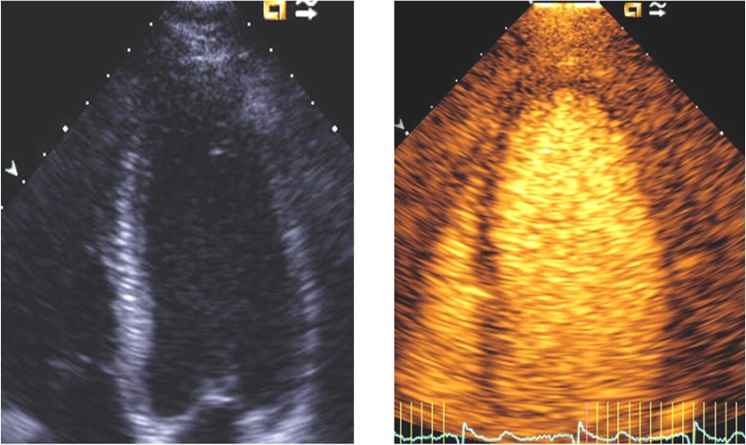

اکوکاردیوگرافی یا همان اکو، یکی از اصلی ترین ابزارهای تشخیص بیماریهای قلبی است. این روش با استفاده از امواج فراصوت، تصاویر متحرکی از قلب ارائه میدهد. با این حال، گاهی اوقات به دلیل عواملی مانند چاقی، بیماریهای ریوی یا ساختار سینه بیمار، تصاویر به دست آمده “کدر” یا “ناواضح” هستند. در چنین مواردی، پزشکان برای دستیابی به تصاویری شفاف و تشخیص دقیق تر، از روش اکو با تزریق کنتراست استفاده میکنند.

اکو با تزریق کنتراست چگونه تصاویر نامشخص را به تصاویری کاملا واضح تبدیل می کند؟ پاسخ در ماده کنتراست و ساختار منحصر به فرد آن نهفته است.

میکروحبابها بازتاب دهندههای بسیار قوی امواج فراصوت هستند. هنگامی که این حبابها به بطن چپ می رسند، حفره را پر از نقاط روشن و سفید می کنند، در حالی که بافت عضله قلب (میوکارد) در اطراف آن خاکستری دیده می شود. این تفاوت در کنتراست، مرز بین خون و عضله را کاملا مشخص می کند.

وضوح بخشی به حفره بطن چپ (LVO)

این هدف اصلی ترین دلیل انجام اکو با تزریق کنتراست است.

_محاسبه دقیق EF قلب: با وضوح یافتن مرزهای داخلی بطن چپ، پزشک میتواند حجم واقعی خون داخل بطن و میزان خونی که پمپ می شود را با دقت بالا محاسبه کند. این امر در مدیریت نارسایی قلبی حیاتی است.